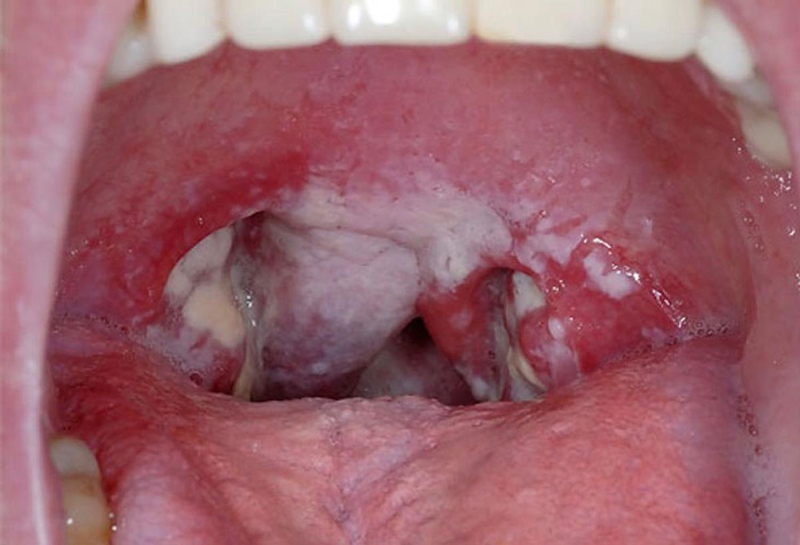

Bệnh bạch hầu là một bệnh truyền nhiễm cấp tính do vi khuẩn bạch hầu hình que hay còn gọi là Corynebacterium diphtheriae gây ra. Bệnh này đặc trưng bởi quá trình viêm và hình thành màng fibrin tại nơi vi khuẩn xâm nhập, đồng thời ngoại độc tố xâm nhập vào máu và gây nhiễm độc cơ thể, gây ra các biến chứng nghiêm trọng như viêm cơ tim, viêm dây thần kinh, suy tim cấp tính và thậm chí là tử vong trong trường hợp nặng với tỷ lệ 5 đến 10% tổng số ca bệnh.